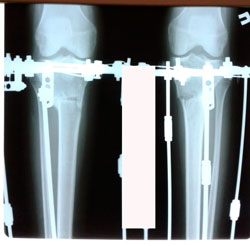

Исходник - 22 года.

Дата операции - 08.06.2020

в процессе круток

Дата снятия аппаратов 24.08.2020

Срок сращения - 75 дней.